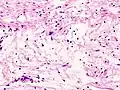

| Micrograph of a schwannoma showing both a cellular Antoni A area (top) and a loose paucicellular Antoni B area (bottom). HE stain. | |

Schwannomas are homogeneous tumors, consisting only of Schwann cells. The tumor cells always stay on the outside of the nerve, but the tumor itself may either push the nerve aside and/or up against a bony structure (thereby possibly causing damage). Schwannomas are relatively slow-growing. For reasons not yet understood, schwannomas are mostly benign and less than 1% become malignant, degenerating into a form of cancer known as neurofibrosarcoma. These masses are generally contained within a capsule, so surgical removal is often successful.[3]

Verocay bodies are seen histologically in schwannomas.

Antoni A area of schwannoma with Verocay bodies (one annotated by circle)_Antoni_B.jpg.webp)